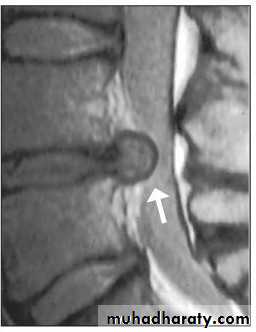

MRI

It is superior to computed tomography (CT) because of its tissue contrast and multi planar capabilities.General objectives of treatment

CT, CT- Myelography

MRl